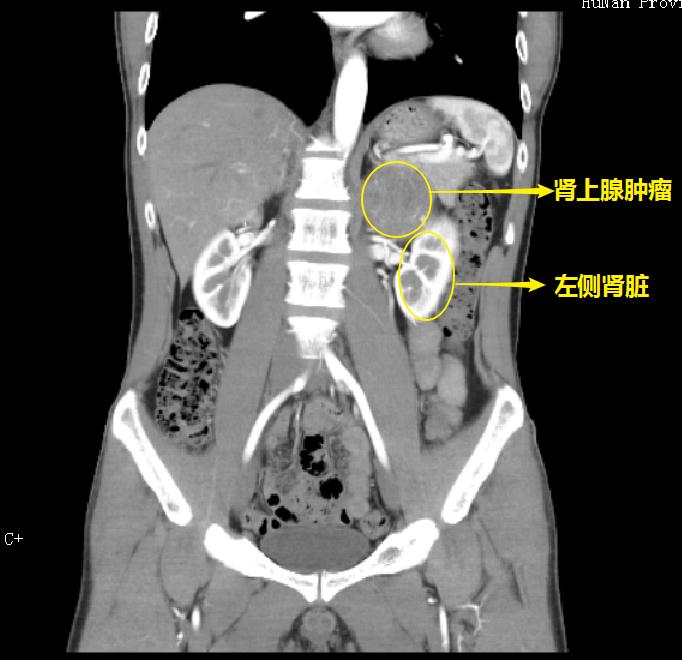

殷先生入院后,CT检查结果显示肿瘤直径约7cm向上推压膈肌和脾脏,内侧推压腹主动脉,手术治疗存在大出血的风险,但如果不及时采取手术治疗,肿瘤在体内如同一个定时炸弹,不仅会继续长大,随时还会使血压急剧升高并发心、脑血管意外危及生命。